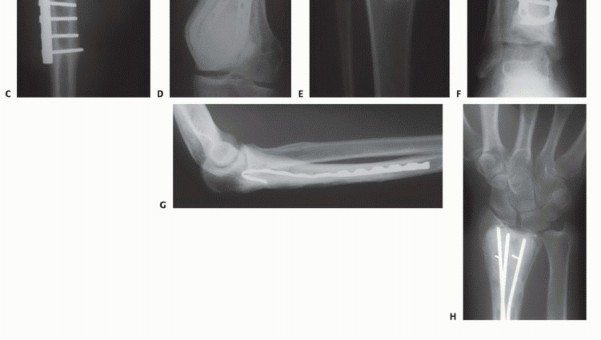

* الكشط والعلاج المساعد (Curettage and Adjuvant Therapy): تُستخدم عادة لأورام العظام الحميدة، حيث يتم كشط الورم من داخل العظم، ثم يتم استخدام مواد مساعدة مثل الفينول أو النيتروجين السائل أو الكي الكهربائي لتدمير أي خلايا ورمية متبقية.

يُعد العلاج بالتبريد، خاصةً بتقنية الصب المباشر بالنيتروجين السائل، ثورة حقيقية في علاج أورام العظام، حيث يقدم بديلاً فعالاً وآمنًا للجراحات الكبرى، مع الحفاظ على الطرف المصاب ووظيفته. يعتمد هذا النهج على تدمير الخلايا السرطانية عن طريق تعريضها لدرجات حرارة منخفضة جدًا، مما يؤدي إلى تجميدها وموتها.

تقنية الصب المباشر بالنيتروجين السائل تفاصيل الإجراء

تعتبر تقنية الصب المباشر بالنيتروجين السائل (Direct Pouring Liquid Nitrogen Technique) في العلاج بالتبريد لأورام العظام من التقنيات المتقدمة التي تتطلب دقة عالية وخبرة جراحية متخصصة. يفضل الأستاذ الدكتور محمد هطيف هذه التقنية نظرًا لفعاليتها في تحقيق تجميد عميق وشامل للورم، مع الحفاظ على الأنسجة السليمة المحيطة.